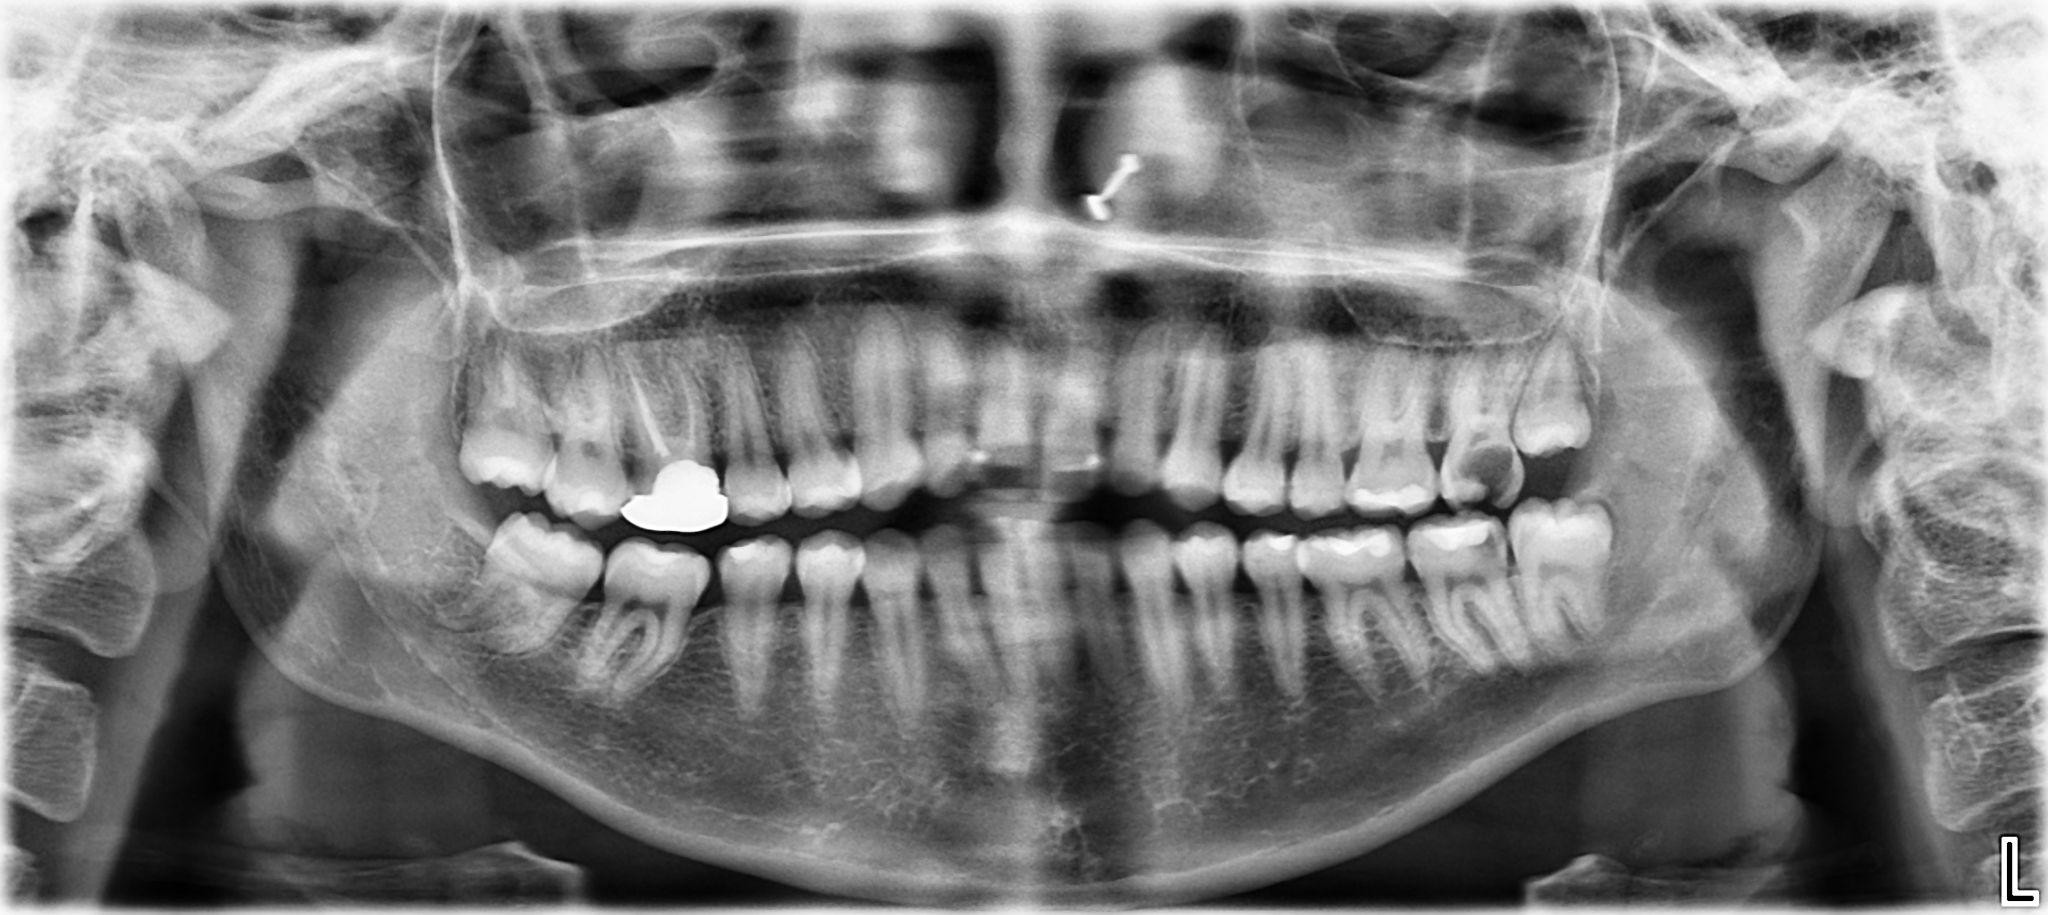

5. What options can be selected for the first quadrant of this panoramic X ray?

6. What options can be selected for the second quadrant of this panoramic X ray?

7. What options can be selected for the third quadrant of this panoramic X ray?

8. What options can be selected for the forth quadrant of this panoramic X ray?